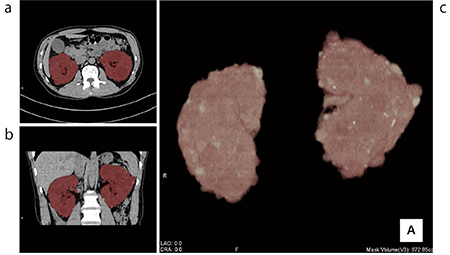

しかし、実際の腎臓の形態は凹凸があり均一ではないため、腎臓容積を計算式のみで正確に算出することは困難である。そこで当院では、今回のZiostation2導入により、CTのthin slice画像から腎臓の容積を3Dで測定するように変更することとなった。Ziostation2では“RealiZe”という新しい三次元形状認識アルゴリズムによって、さまざまな器官の形状の認識、接近する器官の分別を行うことが可能となっている。今回対象となるADPKDについても1クリックで自動抽出が可能であり、従来の処理と比べて作業時間を大幅に短縮することが可能となった。測定方法は、標準の3D解析を起動して腎臓抽出を行い、必要に応じて修正を加える。次にCT値が−50HU以下の脂肪部分を省く。左右の腎臓について、おのおの処理を行い合算された値が両腎の容積となる(図6)。

図6 多発性囊胞腎の容量計測

a:axial b:coronal c:VR